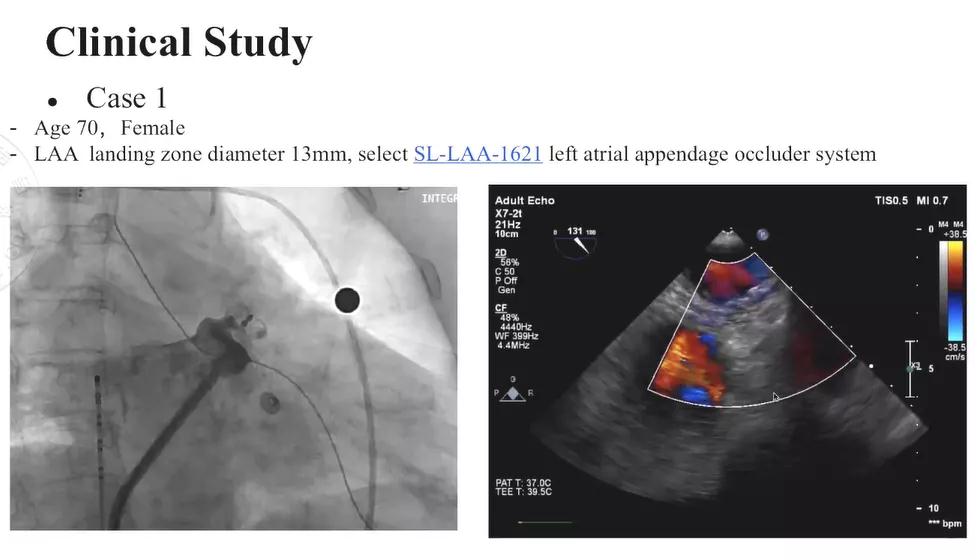

Horst Sievert教授介绍了两例典型的使用SeaLA®封堵器的病例,一例患者为70岁女性,术前进行了经食道超声以及造影检查以评估左心耳形态,左心耳植入区域的直径为13mm,使用的是16-21mm的SeaLA®封堵器。